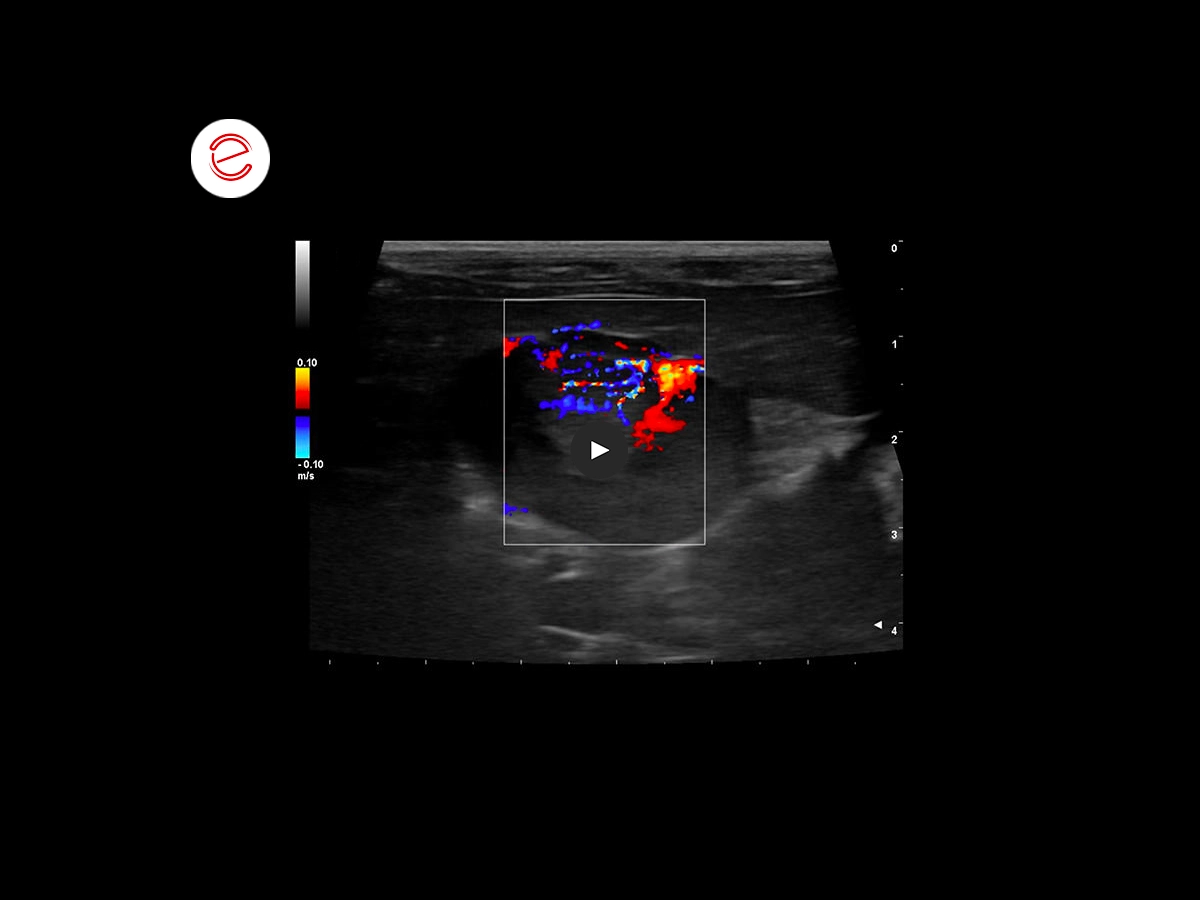

The ultrasound image acquired with Color Doppler mode highlights the significant vascularization of the neoformation with relative flow direction.